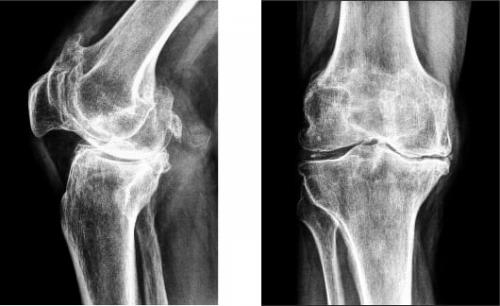

На изображении справа заметно сращение суставной щели.

Гонартроз коленного сустава на рентгене.